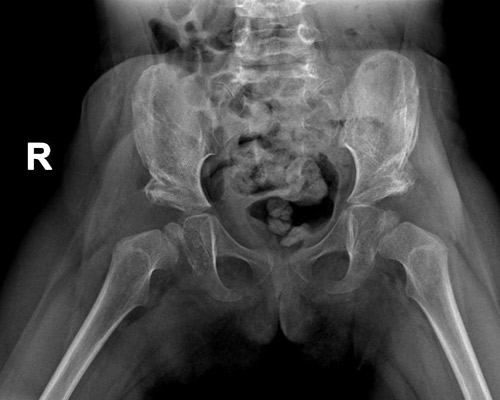

وقال: هناك عدة طرق لاكتشاف المرض وذلك من خلال الكشف السريري لدى الطبيب المختص في جراحه عظام الأطفال والتأكد بأخذ أشعة عادية للحوض تبين من خلالها درجة خلع الورك وما يحتاجه من علاج.